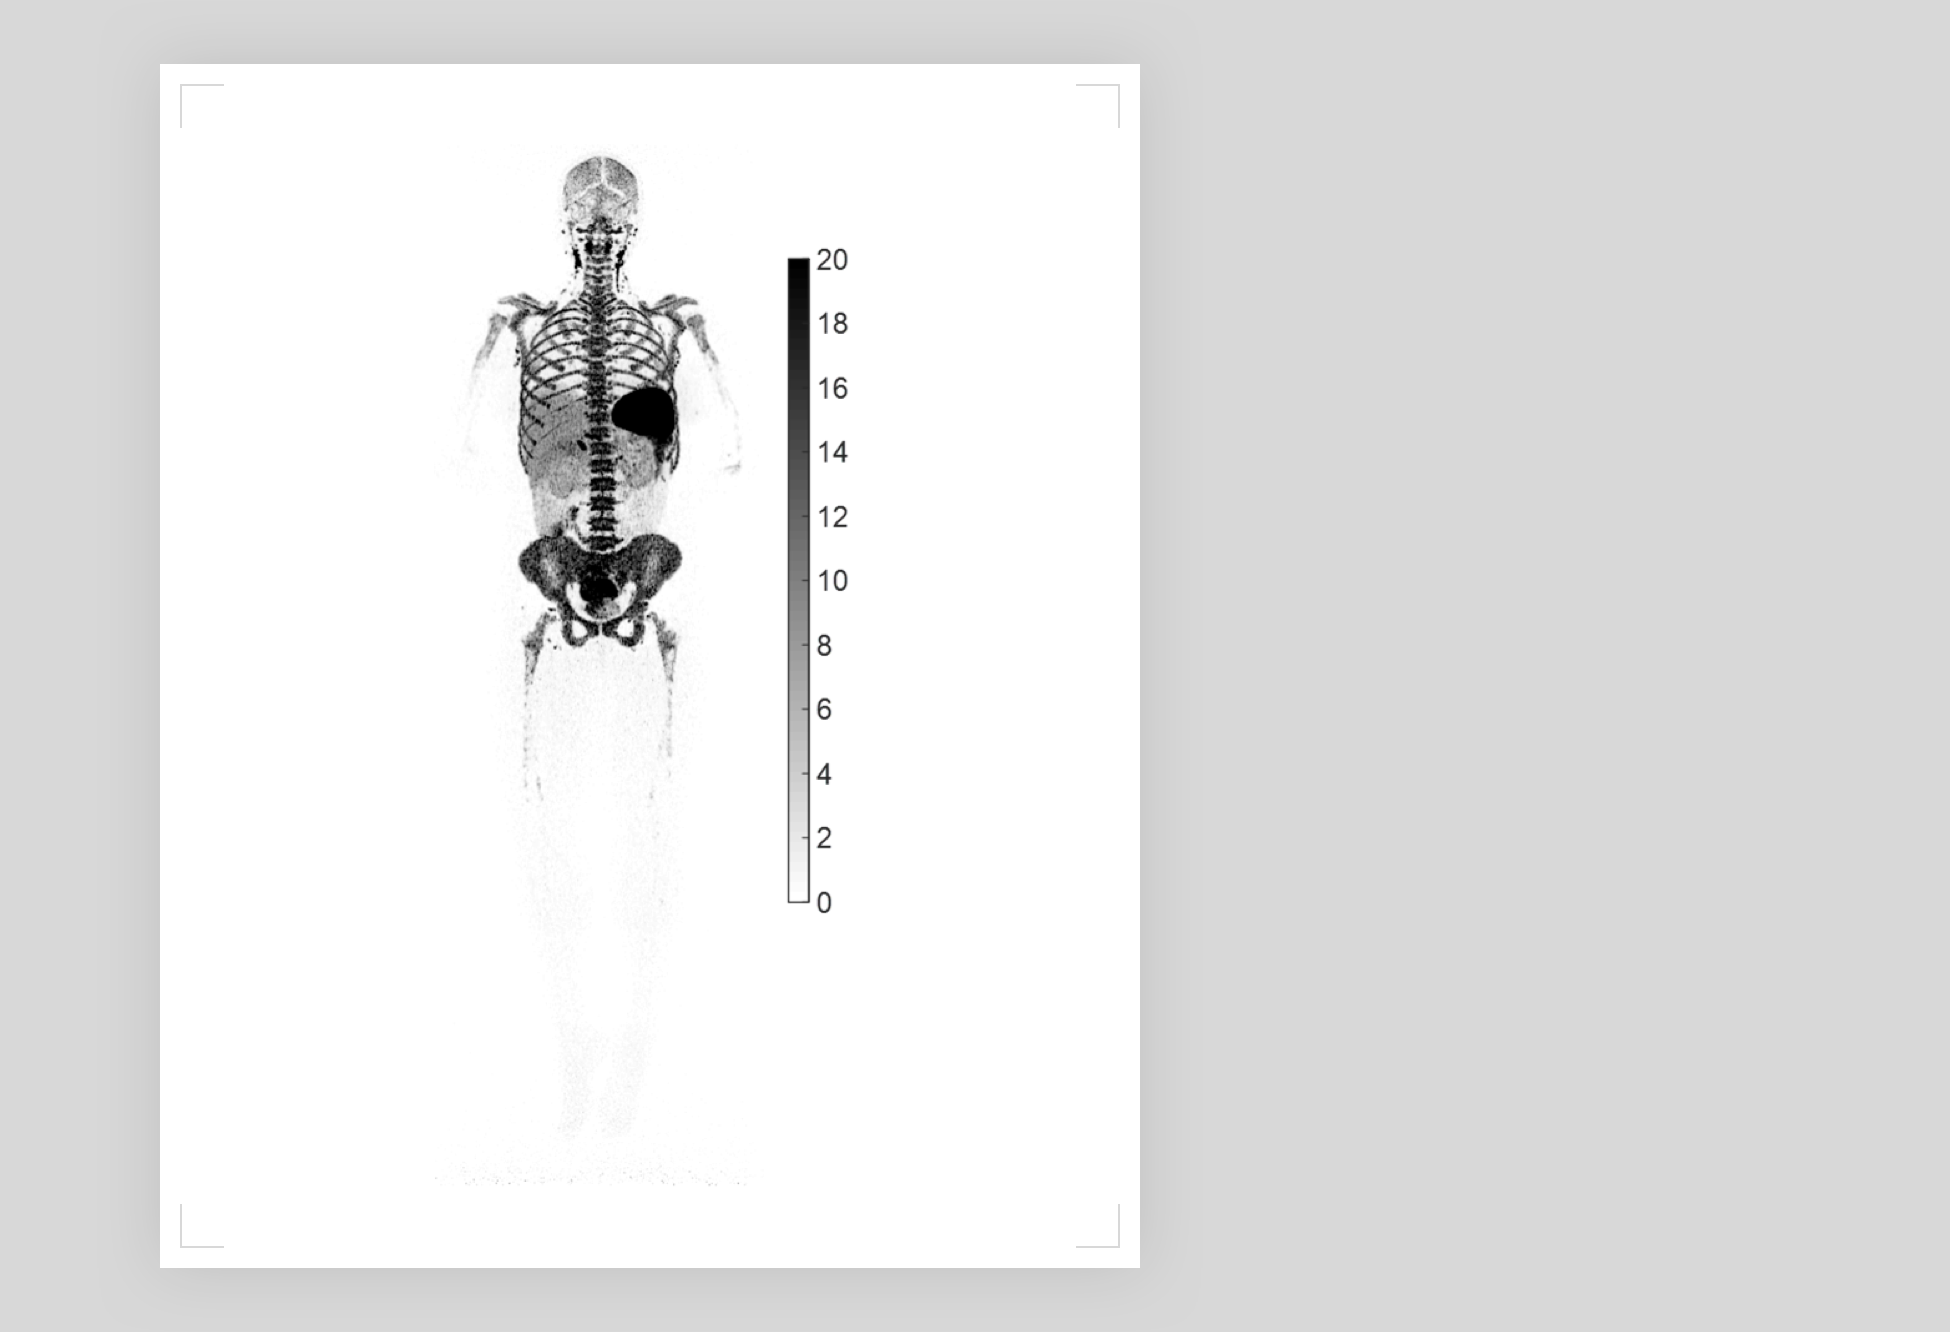

新冠患者全身T细胞无创可视化

新冠患者全身T细胞无创可视化

2022 SNMMI(核医学与分子影像协会)年会上,世界顶尖学府加州大学戴维斯分校(以下简称:UC Davis)公布了关于COVID-19感染的最新研究成果:基于Total-body PET-CT uEXPLORER探索者,人类首次实现新冠患者全身T细胞无创可视化。